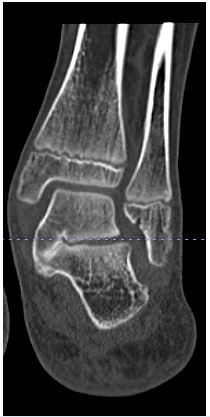

CLO was performed using the established surgical technique described by Mosca [17], (Figure 2A & B). At the conclusion of the procedure, a below-knee plaster of Paris splint was applied. At the first outpatient follow-up visit, 2 weeks postoperatively, the splint was converted to a circular plaster of Paris cast and maintained for an additional 4 weeks.

Figure 2: Pre-operative radiograph (A); Calcaneal lengthening osteotomy with corrected talo-navicular coverage (B).